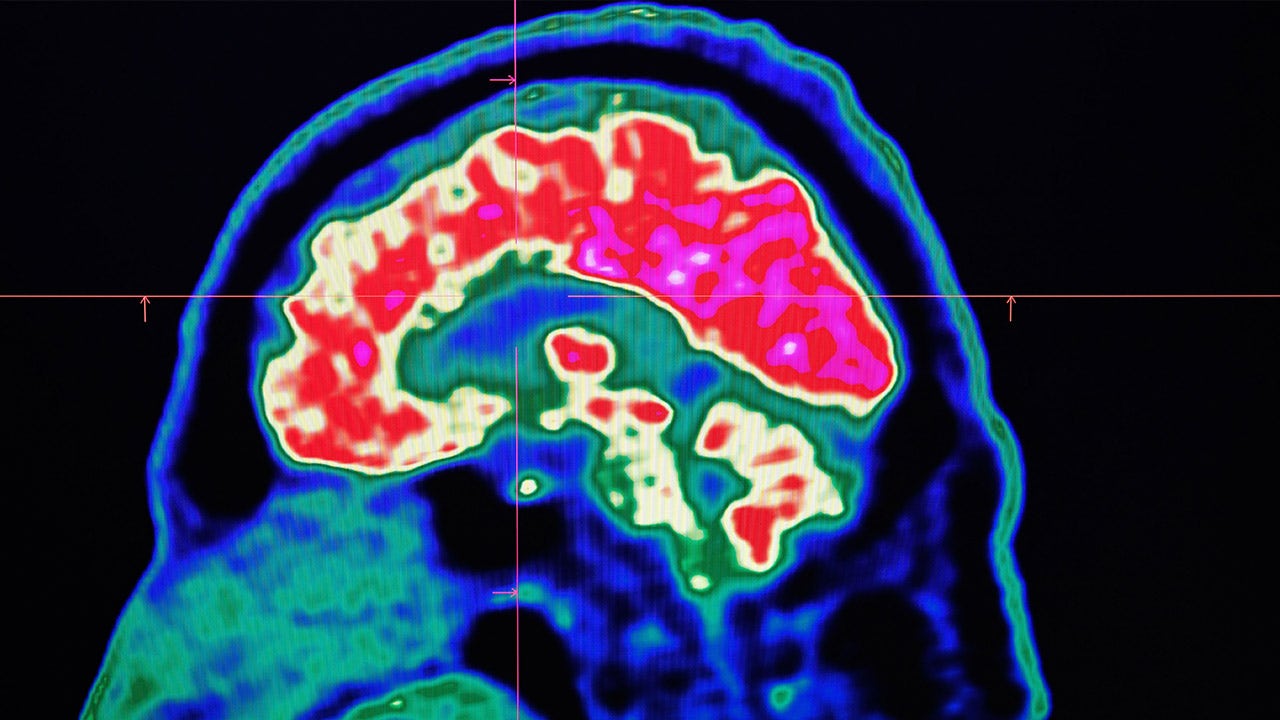

Researchers at the National Institutes of Health recently mapped out the brain activity that flows when we learn a new skill, such as playing a new song on the piano, and discovered why taking short breaks from practice may be a key to learning.

In a study published Tuesday and conducted at the NIH Clinical Center, researchers found that during rest the volunteers’ brains rapidly and repeatedly replayed faster versions of the activity seen while they practiced typing a code.

The team used a highly sensitive scanning technique, called magnetoencephalography, to record the brain waves of 33 healthy, right-handed volunteers as they learned to type a five-digit test code with their left hands.

The authors said the results suggest that regions of the brain are rapidly communicating with the sensorimotor cortex when learning these types of skills. This may result and support the idea that manipulating replay activity during waking rest may be a powerful tool that researchers can use to help individuals learn new skills faster and possibly facilitate rehabilitation from stroke.